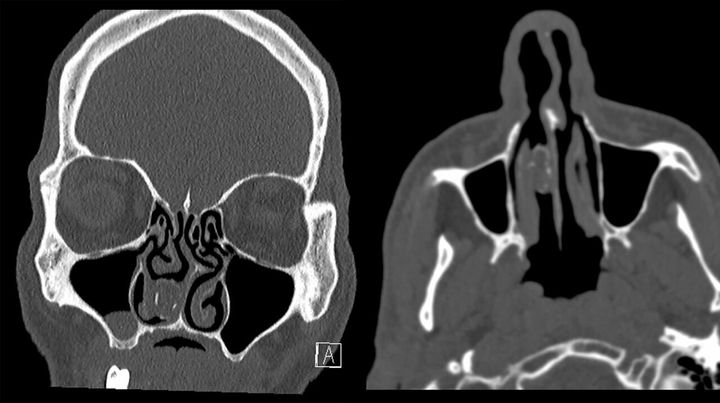

Σύμφωνα με τις εξετάσεις στις οποίες υποβλήθηκε, ένα μικρόβιο είχε προσβάλει την ρινική του κοιλότητα.

Οι γιατροί τελικά αφαίρεσαν την κάνναβη, ενώ ο άνδρας οδηγήθηκε στον Εισαγγελέα για να ανακριθεί.

Εκείνος για να κρύψει την ουσία και να τη μεταφέρει, την έβαλε στο δεξί του ρουθούνι, αλλά τελικά κατέληξε να μην θυμάται τι απέγινε αφού μεγάλο τμήμα της ποσότητας αυτής το εισέπνευσε.

Στη συνέχεια το ξέχασε παρά το γεγονός ότι υπέφερε από προβλήματα στην εισπνοή.

Ο άνθρωπος αναπνέει πλέον ευκολότερα αφού υποβλήθηκε σε επέμβαση.